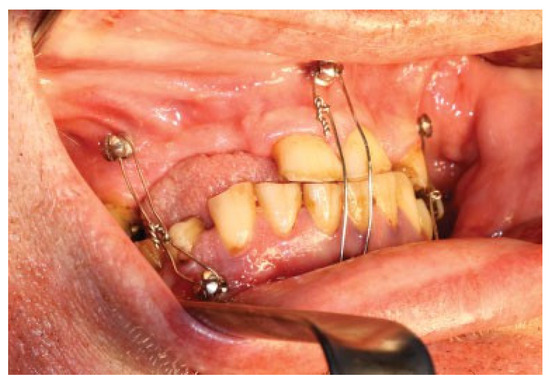

Figure 9.

The patient was placed in MMF during the procedure, enhancing the planned virtual rotations of segments in real life (posterior rotations of the proximal segments 4 degrees and anterior rotation of the distal segment of the mandible).